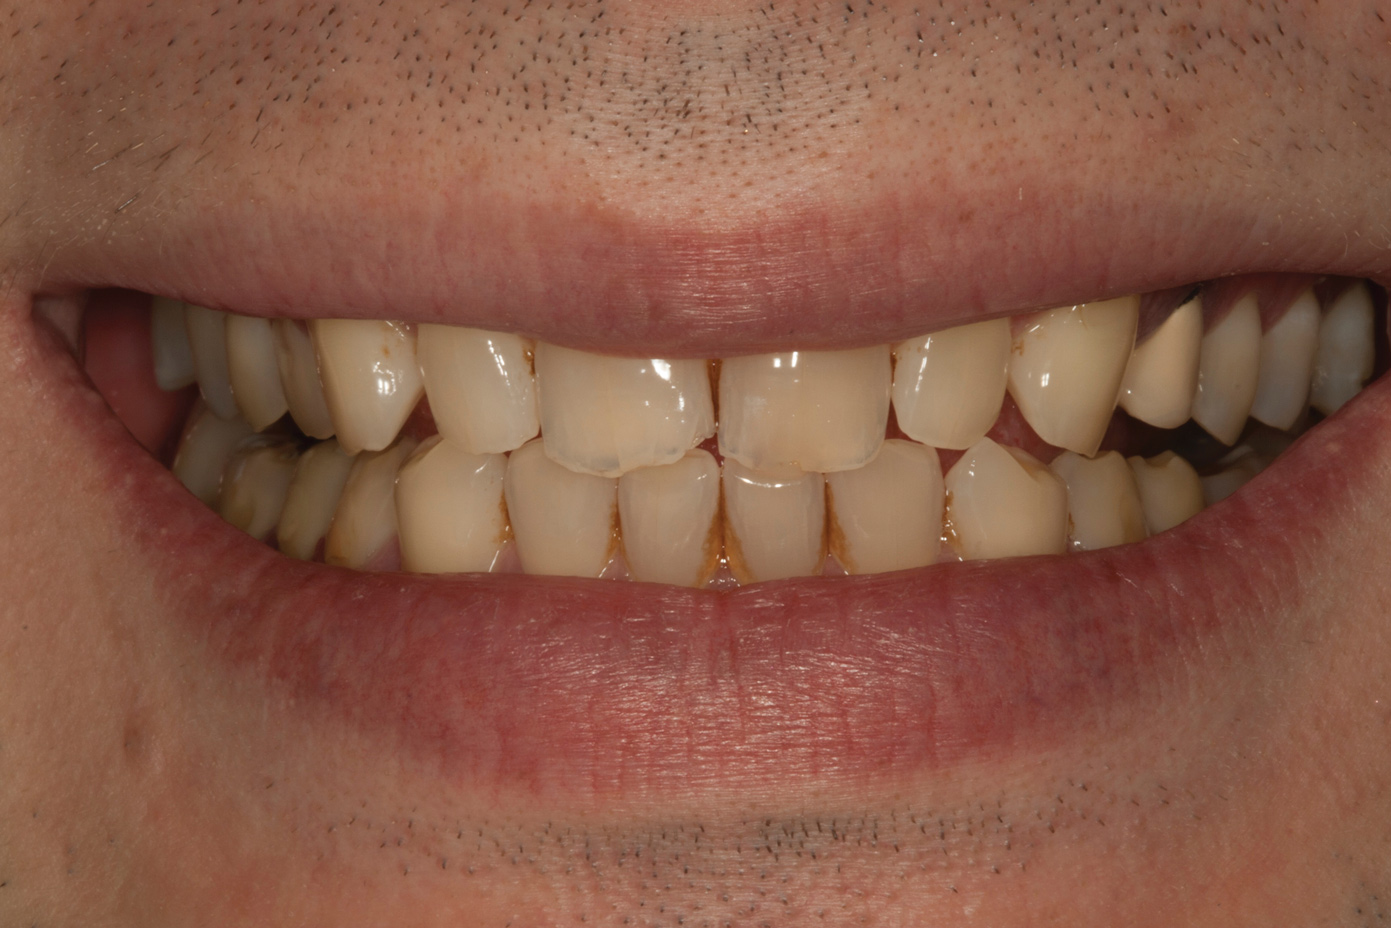

Fig 1. Preoperative smile photograph.

Figure 1

A 34-year-old male patient with no medical issues presented to the office with the chief complaint of a failing crown on tooth No. 12. The patient was also unhappy with his bite and the appearance of his teeth (Figure 1 and Figure 2).

A comprehensive examination was carried out, and preoperative photographs were taken (Figure 1 through Figure 4). The patient presented with fair oral hygiene and slight, generalized tissue inflammation. Caries and defective restorations were detected on teeth Nos. 4, 5, 13, and 14. The crown on tooth No. 12 was showing signs of leakage, and although the endodontic access cavity had been temporarily restored with composite, this endodontic re-treatment was acceptable and the tooth was otherwise symptom-free. Erosion was present on most of the posterior teeth and the cuspids, and abrasion was noted on teeth Nos. 4, 5, 10, 11, 20, 21, 22, 28, and 29. An examination of the patient's muscles, joints, and bite revealed no joint sounds, a normal range of motion, and negative joint load and immobilization tests.

The dentofacial examination revealed a low smile line with no incisor display when the lips were in repose. The anterior teeth were chipped and worn, and their overall color was darkened. The buccal corridors were deficient, and the failing crown on tooth No. 12 was visible in a full smile.